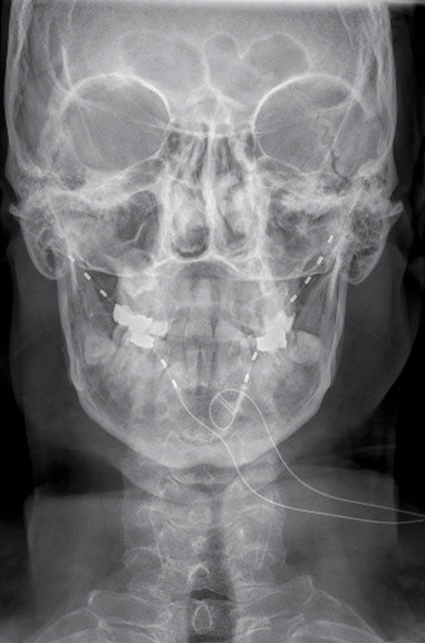

Klassisches Anbindungsgebiet der Feldstimulation ist die Occipitalisstimulation. Ein inzwischen sehr gut untersuchtes Verfahren zur Therapie des klassischen Clusterkopfschmerzes. Dabei werden die Stimulationselektroden occipital über das Versorgungsgebiets des Nervs verlegt (Abb. 3). Im Rahmen der Stimulation kommt es zu einer Reduktion der Anfallshäufigkeit sowie der Schmerzintensität. Im Rahmen der multimodalen Schmerztherapie, besonders bei Kopfschmerzpatienten, ist dies eine gute Möglichkeit, die sogenannten trigeminoautonomen Kopfschmerzerkrankungen zu therapieren. Chronische Rücken- oder Nackenschmerzen, vor allem nach ausgedehnten Wirbelsäulenoperationen, lassen sich durch Stimulationssonden im Bereich der Subkutis lindern. Die wenig invasiven Maßnahmen eignen sich sehr gut für eine Teststimulation, da diese noch weniger invasiv sind als die probatorische Rückenmarksstimulation. Auch hier sollten vorher alle konservativen Maßnahmen ausgeschöpft worden sein. Eine psychologische Mitbetreuung ist unabdingbar.